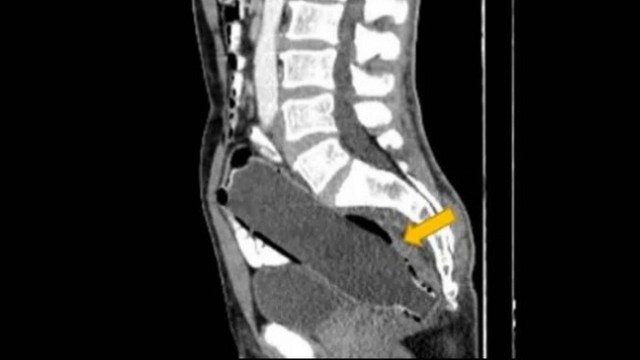

Após o homem ser submetido a uma tomografia computadorizada, a verdade veio à tona. O resultado apontou que havia uma garrafa de 250ml entalada no seu reto. O vasilhame ficou lá por três dias até que as dores insuportáveis fizeram o iraniano aceitar ir à emergência de um hospital.

O fundo da garrafa já estava entrando no cólon (intestino grosso), enquanto a boca da garrafa estava a cerca de 10mm da abertura do ânus.